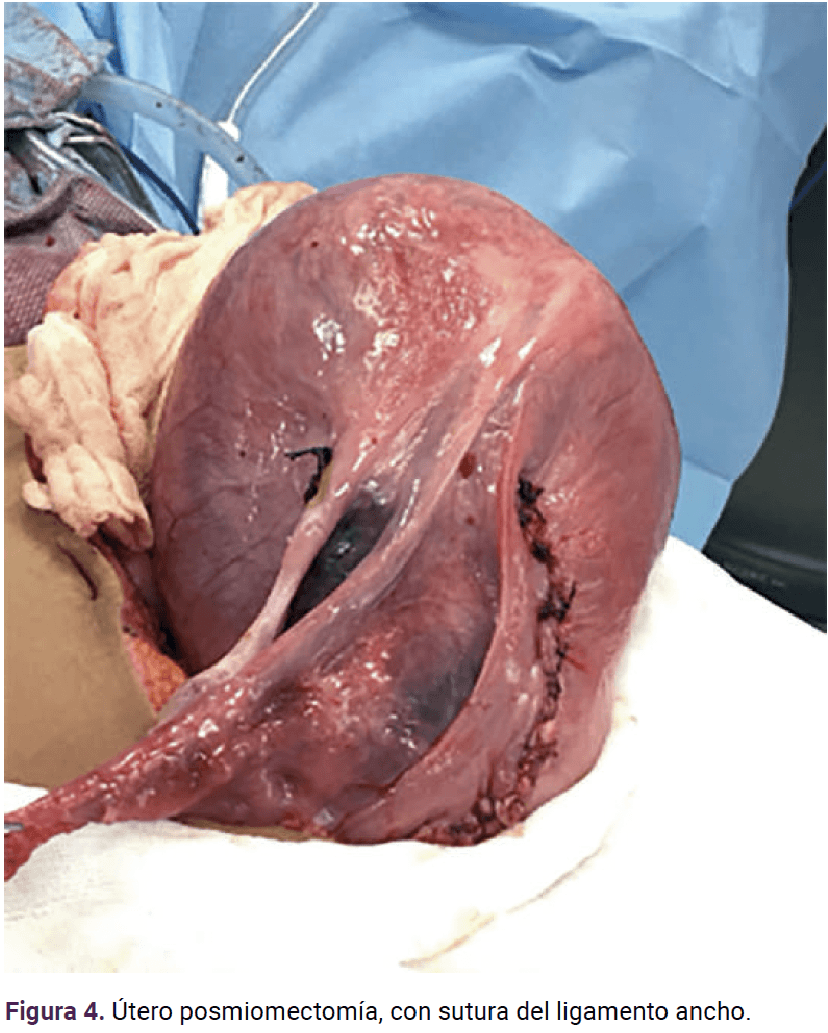

Paciente de 19 años, primigesta, con antecedente heredofamiliar (tía paterna) de cáncer de ovario. Acudió a consulta para control prenatal a las siete semanas de gestación, con dolor abdominal y crecimiento rápido de un tumor abdominal. Durante la exploración física el abdomen se palpó globoso, a expensas del tumor abdominopélvico, a 2 cm por arriba de la cicatriz umbilical, móvil, con dolor a la palpación media y profunda. El ultrasonido reportó un mioma subseroso de 15.4 x 7.3 cm y la resonancia magnética concluyó que se trataba de un mioma con diámetro mayor de 24 centímetros que desplazaba y comprimía la cavidad amniótica (Figura 1). En la interconsulta con el ginecooncólogo se planteó la posibilidad de complicaciones conforme el mioma fuera creciendo; por ello se decidió la miomectomía abierta en el segundo trimestre de la gestación. La miomectomía se llevó a cabo, sin ingreso a la cavidad uterina, a las 21.4 semanas y se extirpó un mioma intraligamentario de 20 x 18 x 11 cm y 2410 g (Figuras 2, 3 y 4) con sangrado de 900 mL y las dificultades propias de un mioma hipervascularizado. El estudio transoperatorio reportó: leiomioma con cambios hidrópicos, negativo para malignidad (mismo diagnóstico del reporte definitivo). Se finalizó el procedimiento y se corroboró la frecuencia cardiaca fetal de 150 lpm. El resto del control prenatal transcurrió sin complicaciones y se finalizó el embarazo a las 38.0 semanas mediante cesárea, indicada por registro cardiotocográfico categoría II (línea basal con bradicardia con mínima variabilidad y ausencia de aceleraciones), sin complicaciones, con sangrado de 300 mL y obtención de una recién nacida de 2515 g, Apgar 8-9. A petición de la paciente se le colocó un dispositivo intrauterino de levonorgestrel, como método de control de la fertilidad.

<strong>Figura 1</strong>

Figura 1.